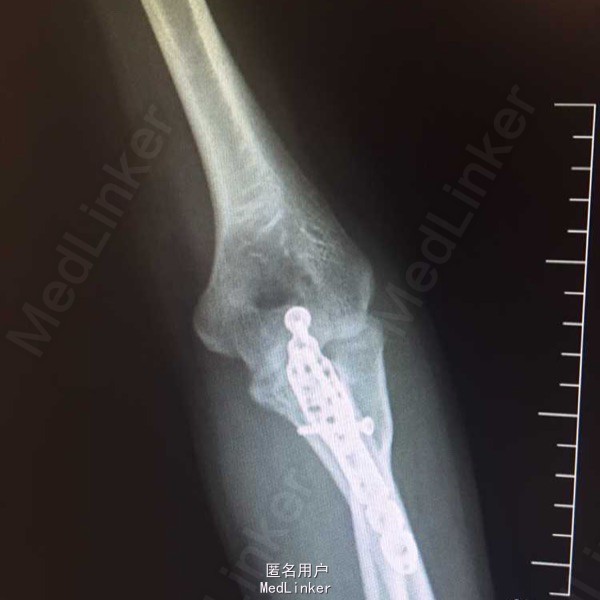

左尺骨鹰嘴粉碎性骨折,专科检查:左肘部肿胀触痛明显,纵向叩击痛阳性,活动受限,左腕部及各指活动正常,末梢感觉正常,桡动脉触动可触及,左上肢肌力、肌张力因疼痛未查。患者因疼痛卧床脊椎未查,左足跟及踝关节肿胀,伴散在丘疹,皮下有瘀血斑,双踝关节主被动活动受限,双下肢肌力,肌张力因疼痛未查。双足足背动脉及胫后动脉搏动正常,双足皮温正常,足趾运动正常。

诊断:1.双侧跟骨粉碎性骨折,2.左尺骨鹰嘴粉碎性骨折3.全身多处软组织损伤。诊疗计划:积极完善入院常规检查及足踝CT三维重建,嘱患者抬高患肢,暂时给予消肿,镇痛等治疗。